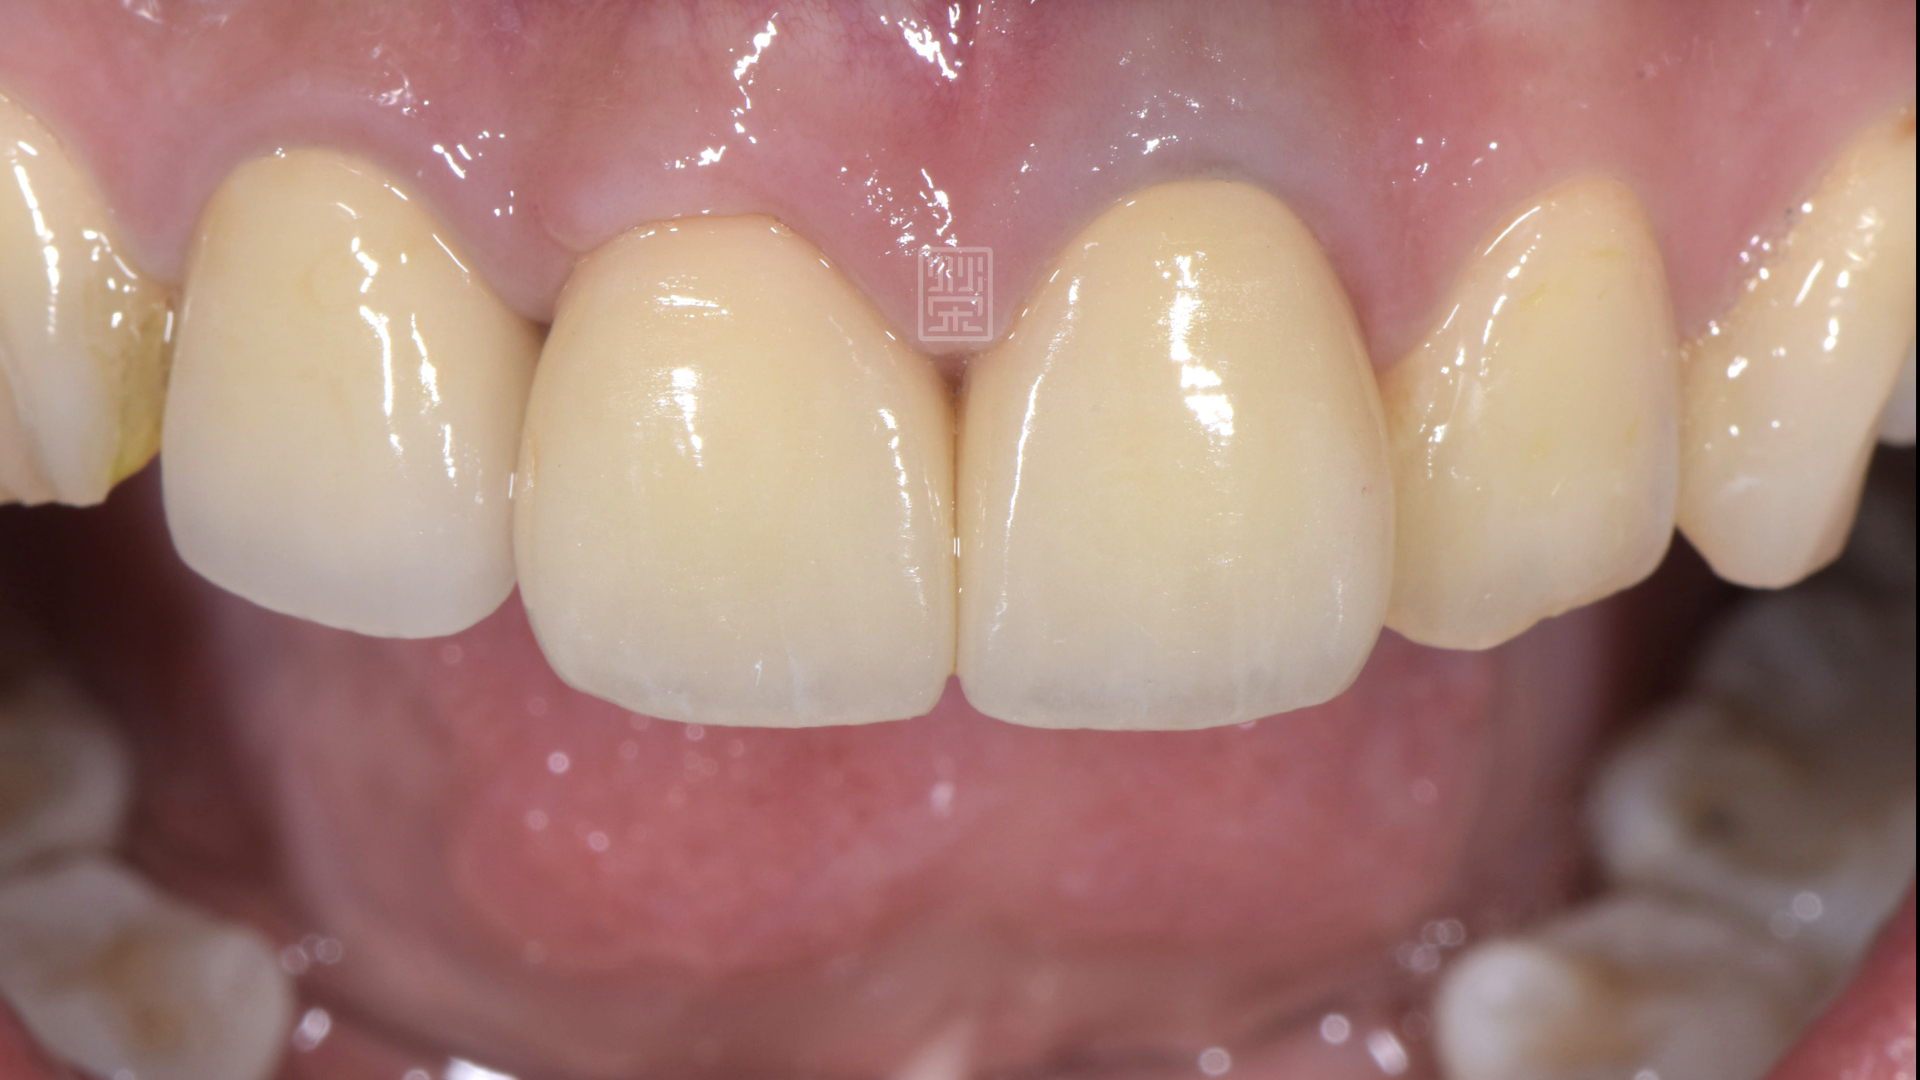

全瓷冠完成